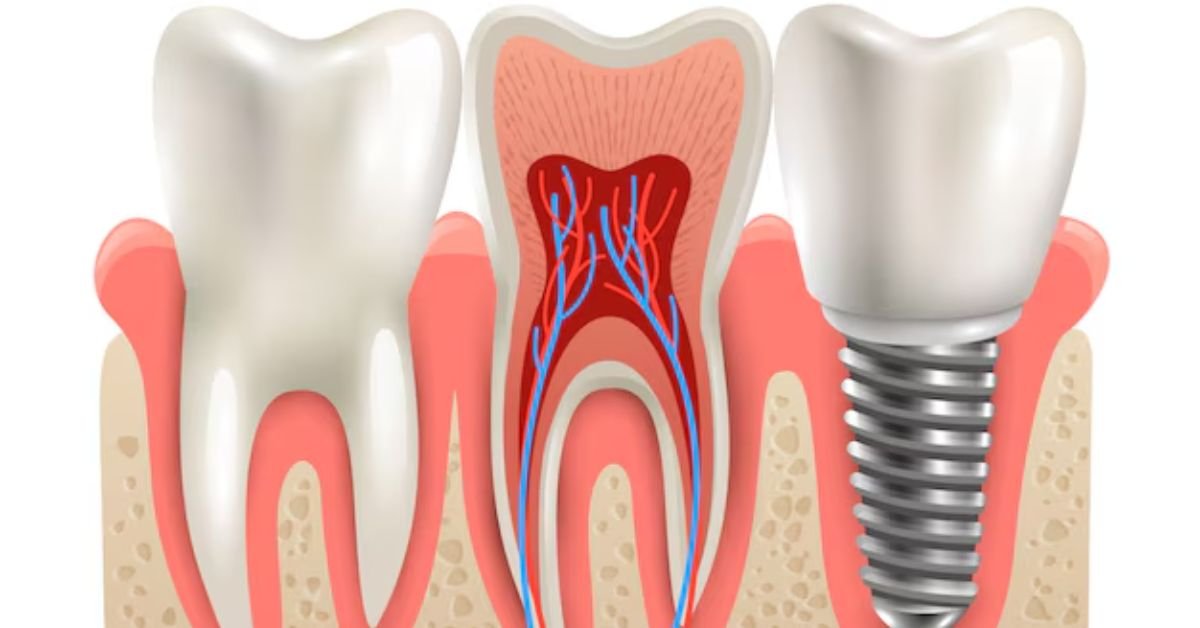

Root canal treatment (also known as endodontic therapy) is a dental procedure used to remove infected or damaged pulp from inside a tooth. The pulp is the soft tissue that contains nerves and blood vessels. When it becomes infected due to decay, cracks, or injury, it can cause severe pain and may lead to tooth loss if untreated.

During the procedure, the dentist:

Removes the infected pulp

Cleans and disinfects the root canals

Fills and seals the space

Often places a crown to restore the tooth’s strength and function